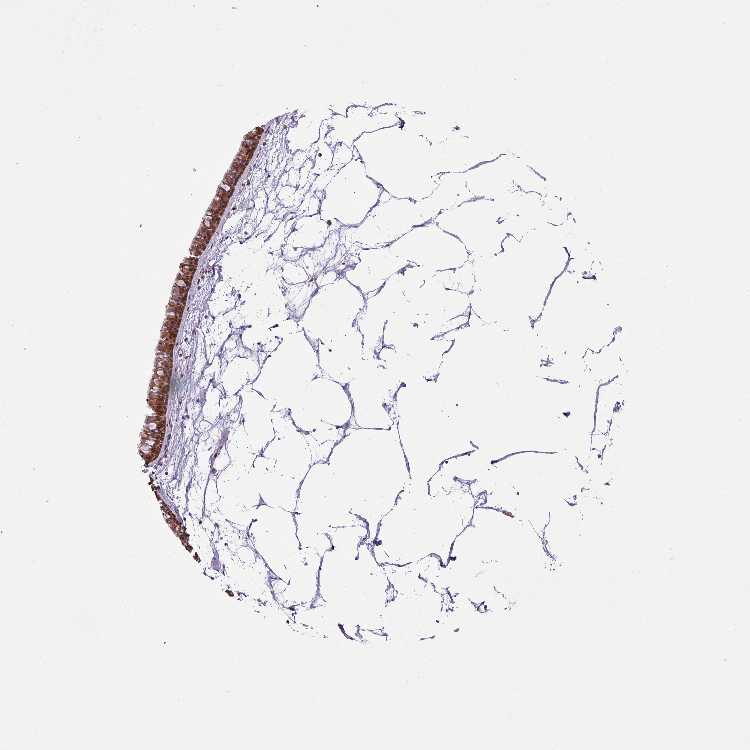

TISSUE PRIMARY DATA NASOPHARYNX Show tissue menu

NASOPHARYNX - Antibody stainingi

Antibody staining in the annotated cell types in the current human tissue is reported as not detected, low, medium, or high, based on conventional immunohistochemistry profiling in selected tissues. This score is based on the combination of the staining intensity and fraction of stained cells.

Each image is clickable and will lead to virtual microscopy that enables deeper exploration of all samples and also displays staining intensity scores, fraction scores and subcellular localization as well as patient and tissue information for each sample.

Antibody HPA051213

Respiratory epithelial cells High